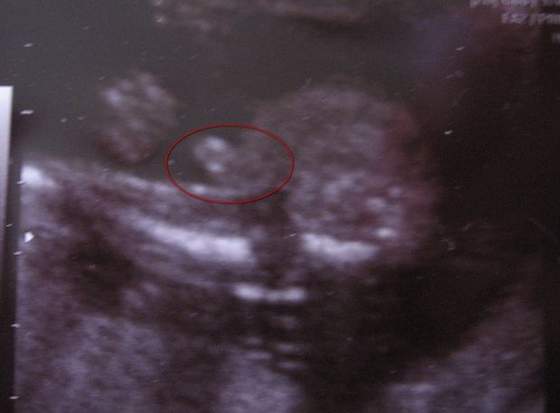

hahaha no ja osobiście to nie mam ;-)ale u dzidzi najwyraźniej już zostanie

Zobacz załącznik 541687